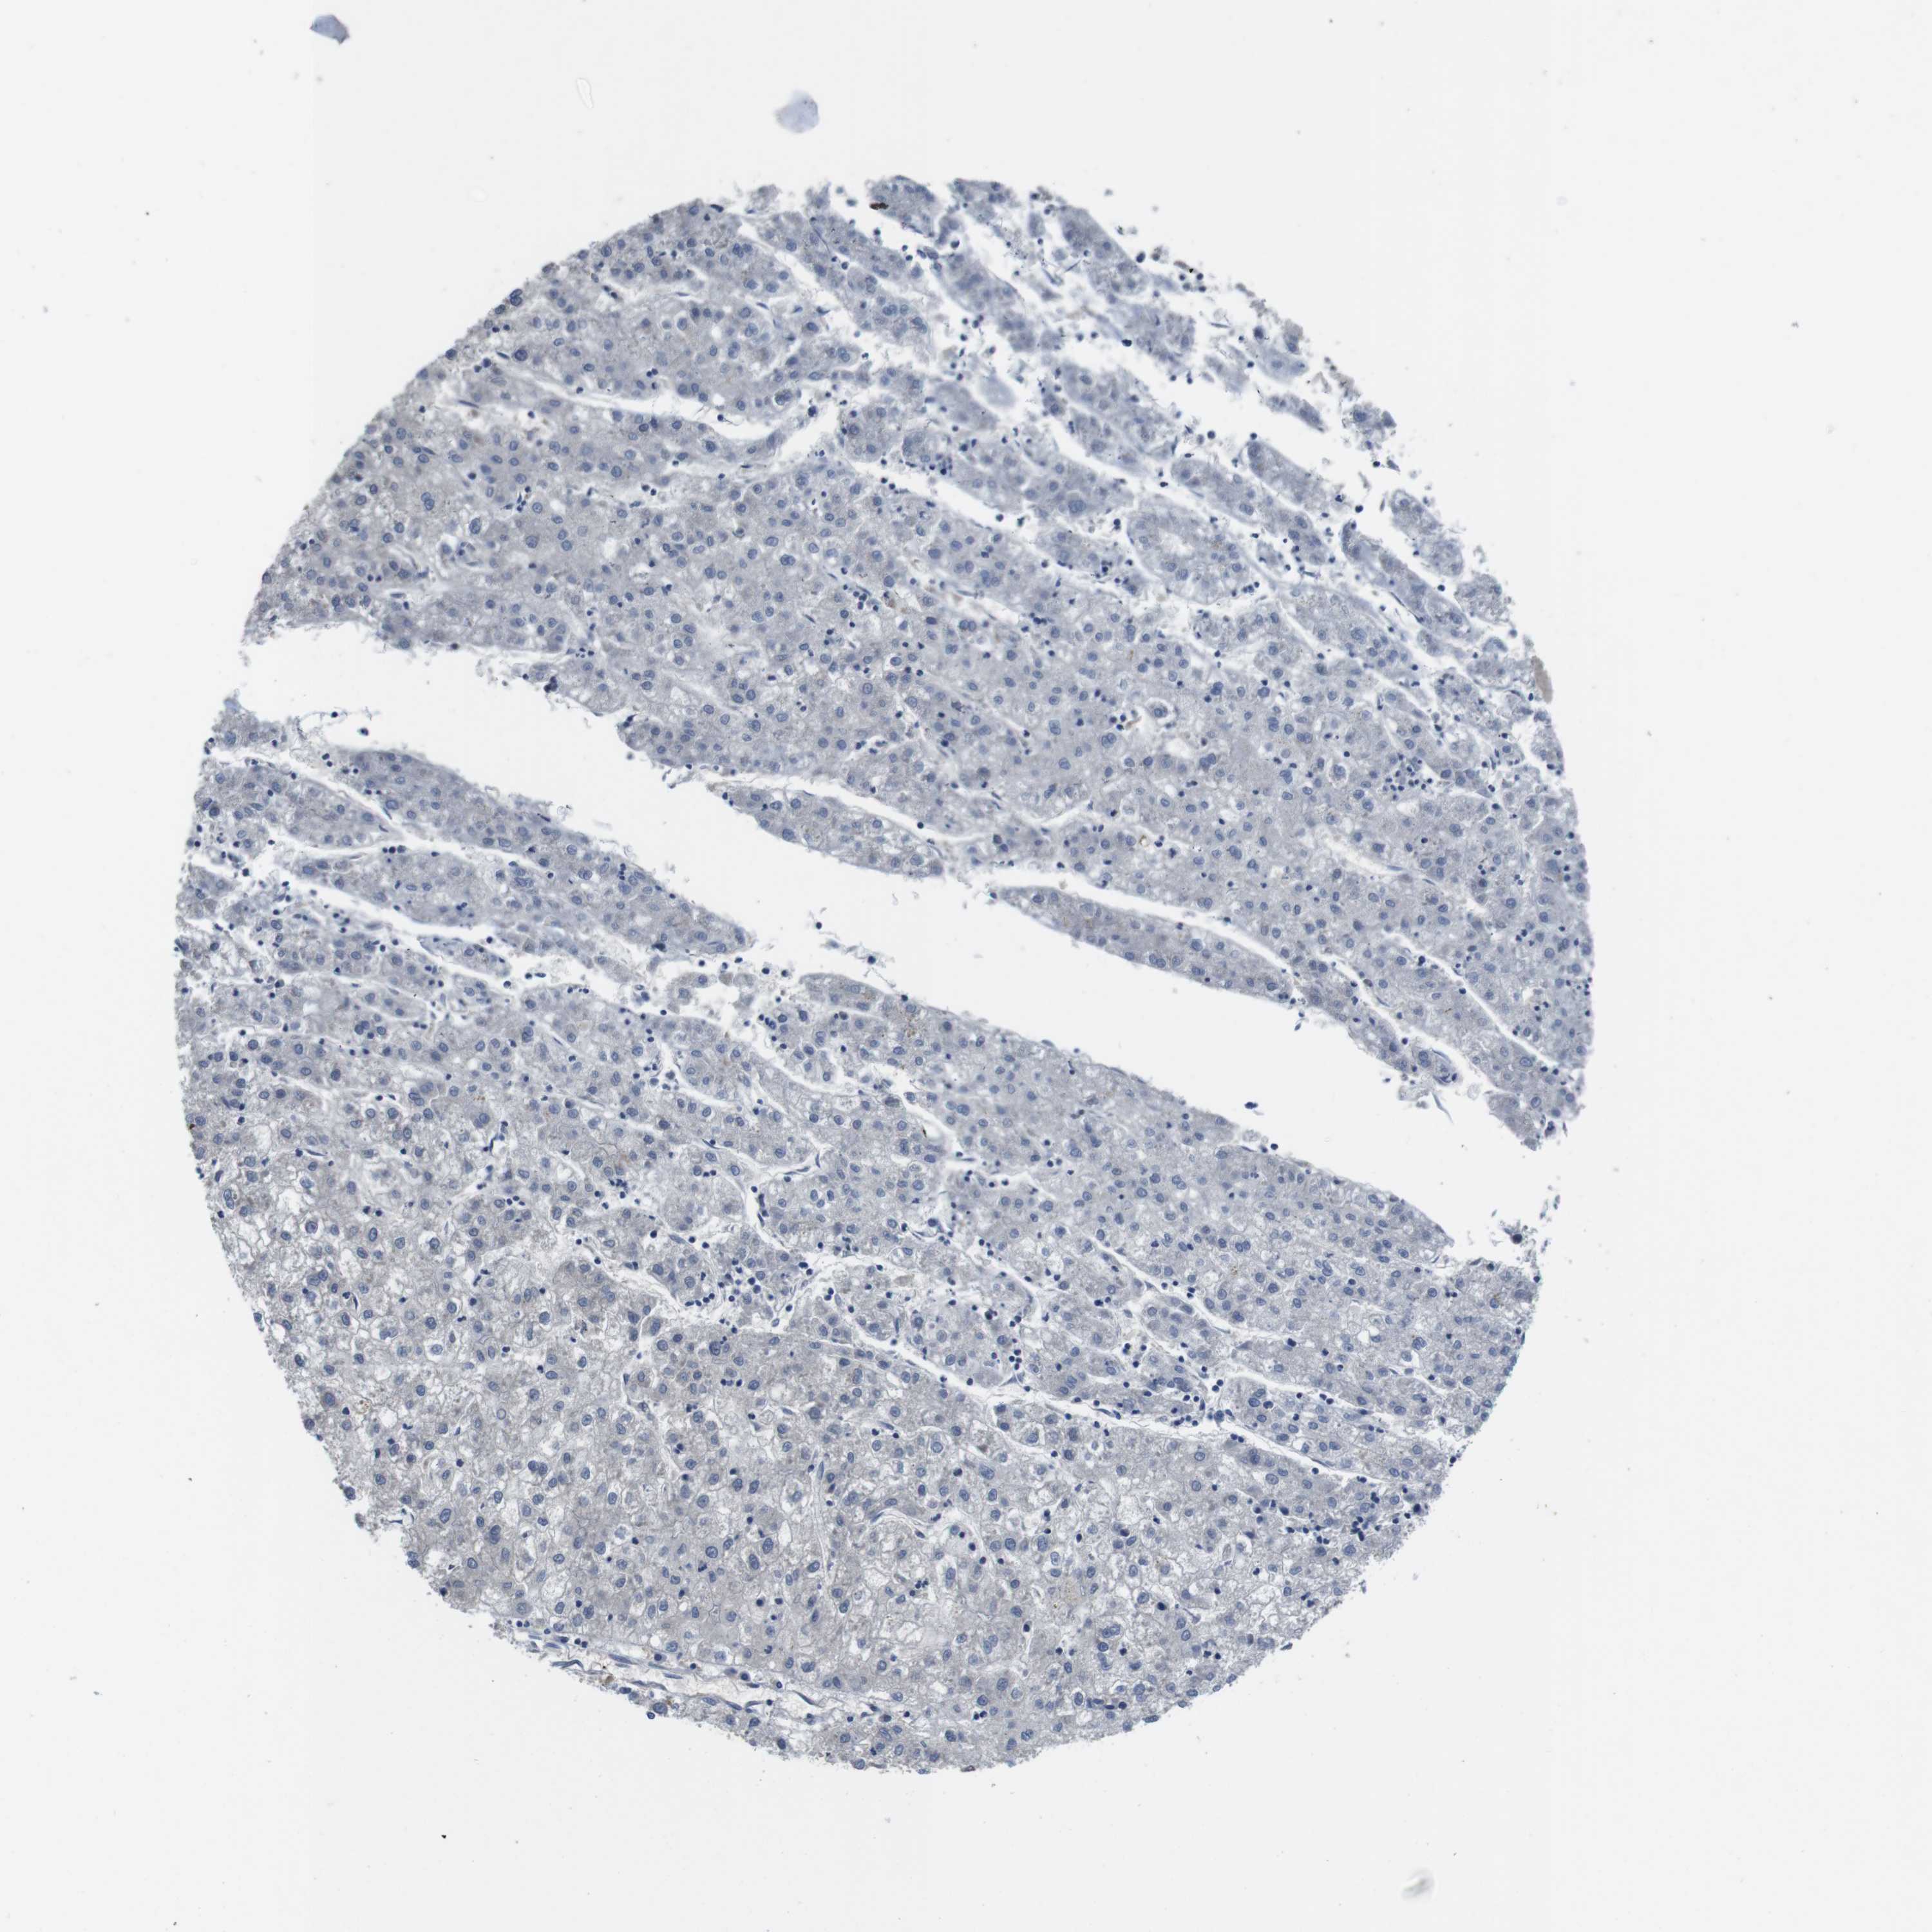

LIVER CANCER - Protein expressioni

A mouse-over function shows sample information and annotation data. Click on an image to view it in a full screen mode. Samples can be filtered based on level of antibody staining by selecting one or several of the following categories: high, medium, low and not detected. The assay and annotation is described here.

Antibody stainingi

Antibody staining in the annotated cell types in the current human tissue is reported as not detected, low, medium, or high, based on conventional immunohistochemistry profiling in selected tissues. This score is based on the combination of the staining intensity and fraction of stained cells.

Each image is clickable and will lead to virtual microscopy that enables deeper exploration of all samples and also displays staining intensity scores, fraction scores and subcellular localization as well as patient and tissue information for each sample.

Antibody HPA001464

Cholangiocarcinoma

Carcinoma, Hepatocellular, NOS